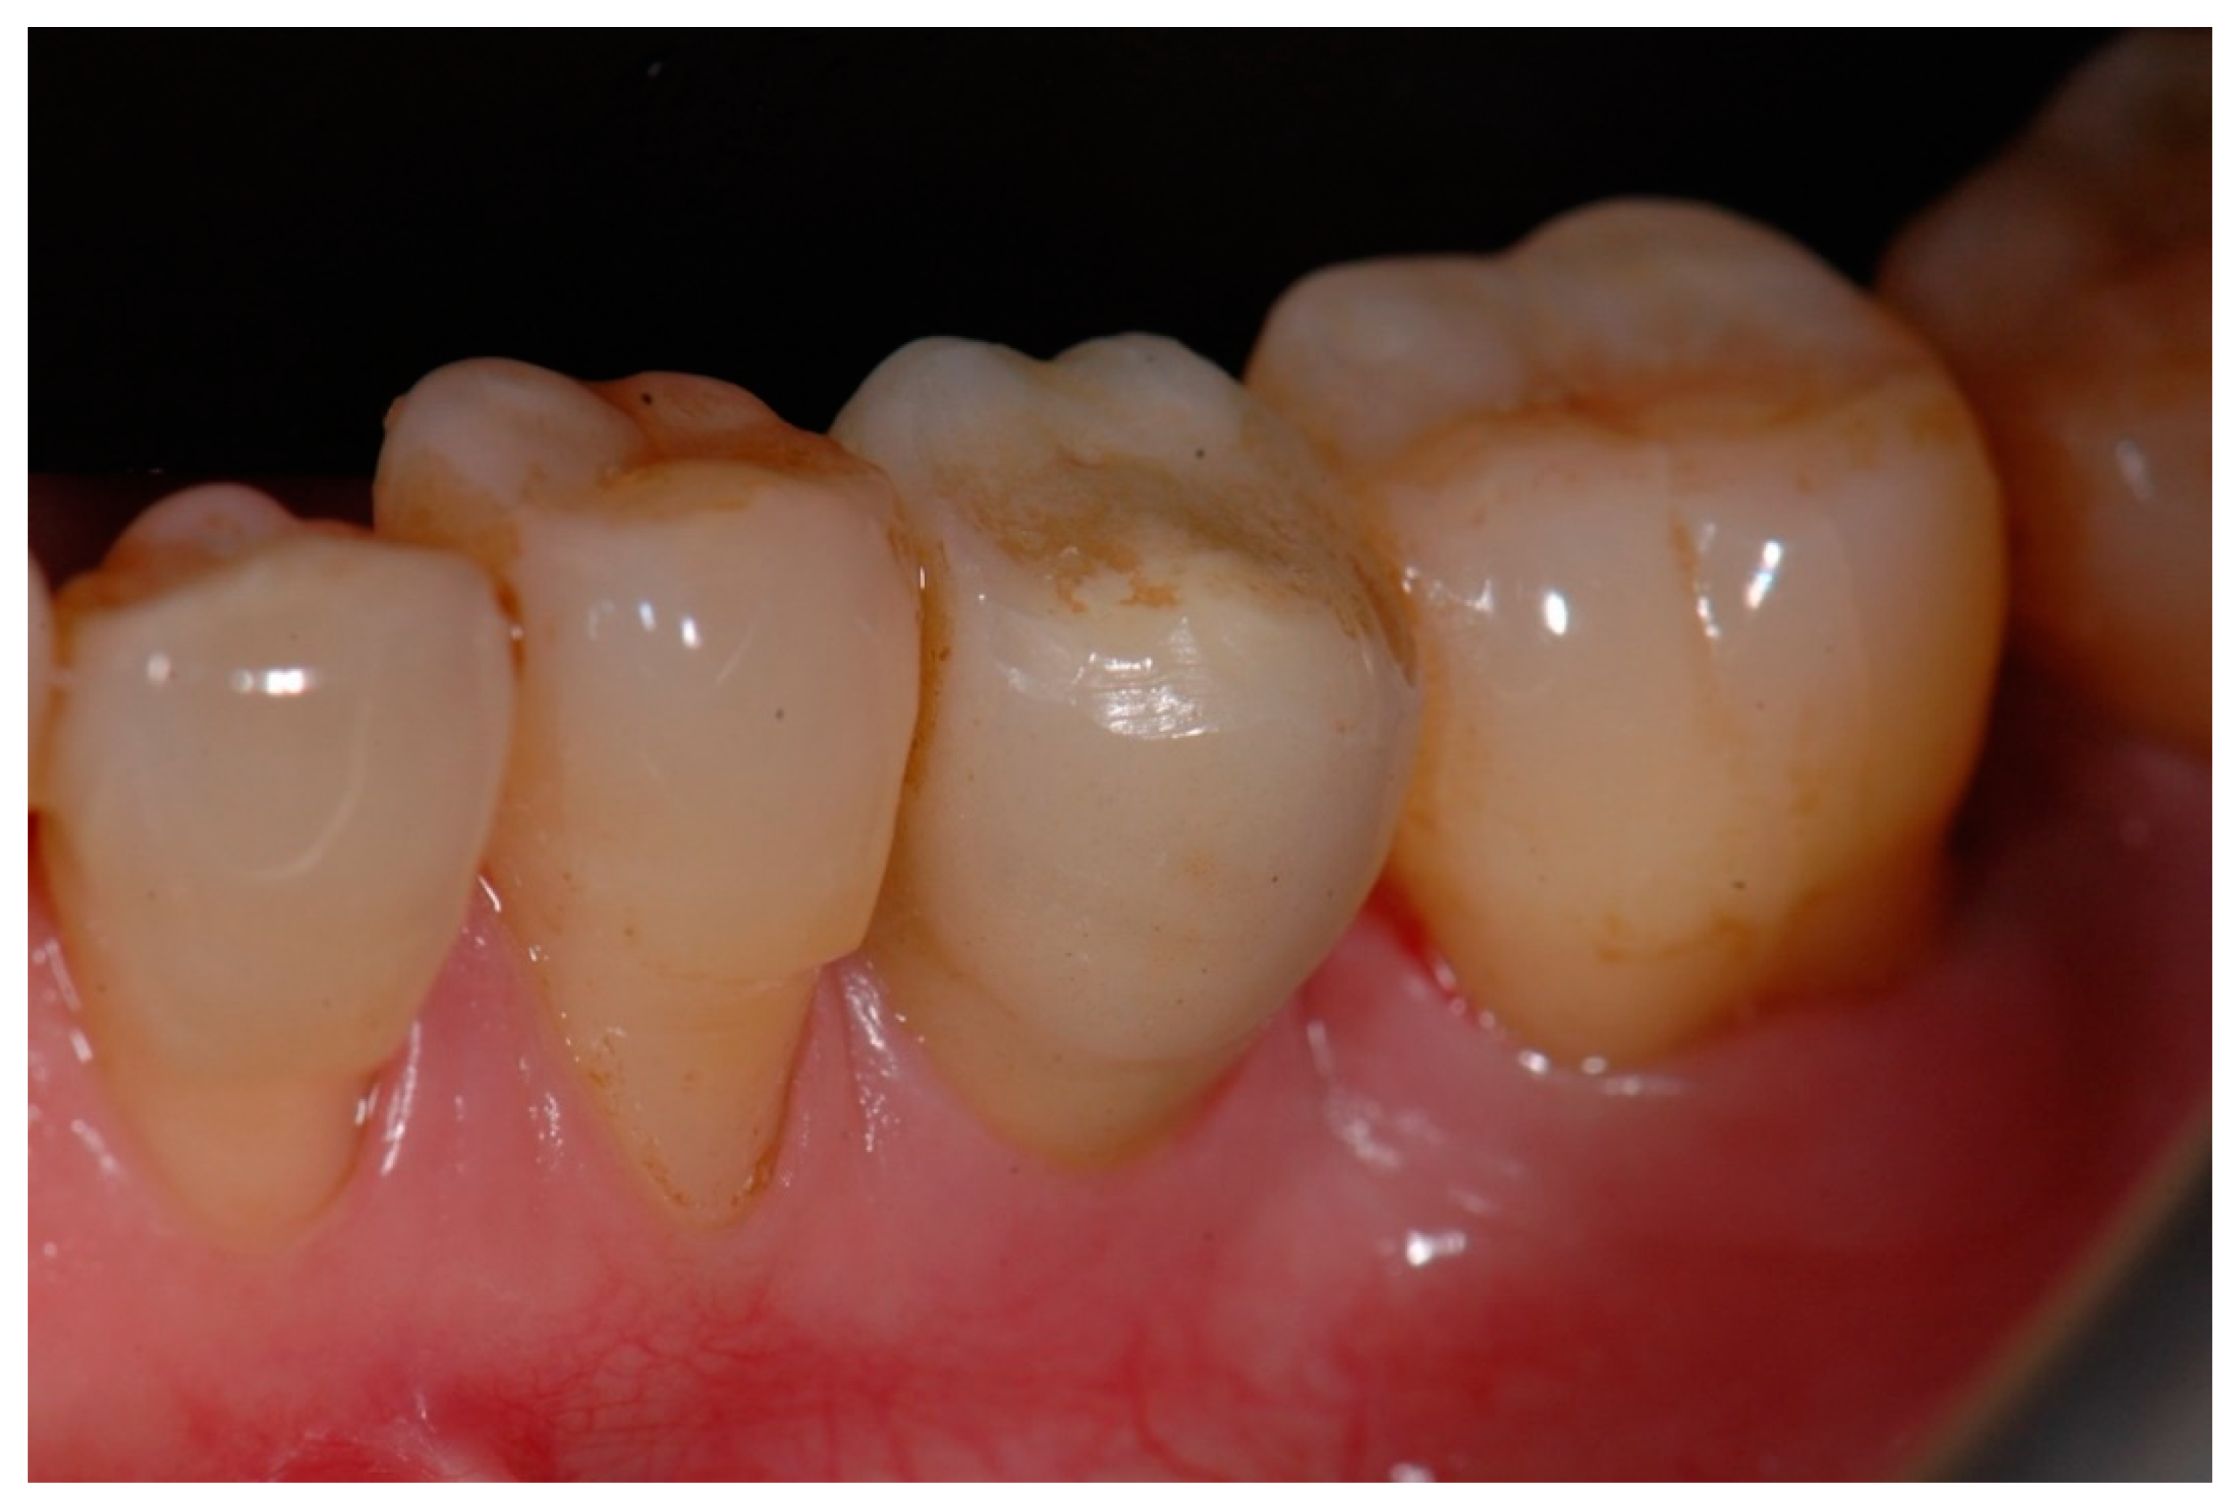

Lastly, Figure 7 and Figure 8 show a definitive ceramic restoration in another case located in the maxillary left first premolar space and its corresponding intraoral X-ray view, after three years of follow-up.

Figure 7. Definitive ceramic restoration in a maxillary left first premolar (after 3 years of follow-up).